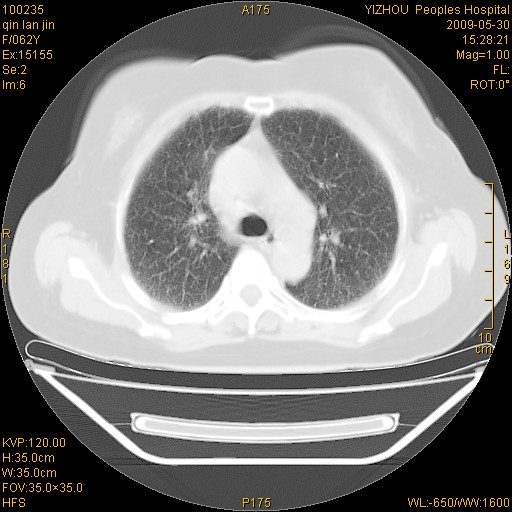

标题: CT20268:肺泡癌?间质性肺炎? [打印本页]

标题: CT20268:肺泡癌?间质性肺炎?

女,62岁,近二年经常咳嗽,近二个月,消瘦、乏力。

弥漫性双肺间质纤维化。

两肺弥漫性间质性病变(间质性肺炎伴肺间质纤维化?)。